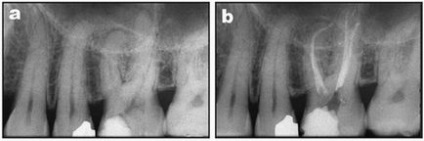

Klinikai eset №2.

a) A második felső állkapocs kisőrlő jobb jeleivel akut gyulladás a cellulóz.

b) Mtwo 20.06 eszköz be a munkahossz.

c, d) kitöltése a gyökércsatorna rendszer előkészítés után Mtwo eszközöket a standard szekvencia és Mtwo A1 (a különböző előrejelzések).

a) Az első felső állkapocs kisőrlő a jelzések endodonciai kezelés. Meghatározása munkahossz egy acél fájlt.

b) kitöltése a gyökércsatorna rendszer előkészítés után csatorna Mtwo eszközöket a standard szekvencia és Mtwo A1.

Klinikai eset №4.

a) a második moláris a maxilla bal jelzések endodonciai kezelés.

b) kitöltése a gyökércsatorna rendszer elkészítése után Mtwo csatorna eszközök szabályos sorrendben

és Mtwo A2.

c) ismételt vizsgálata egy év.